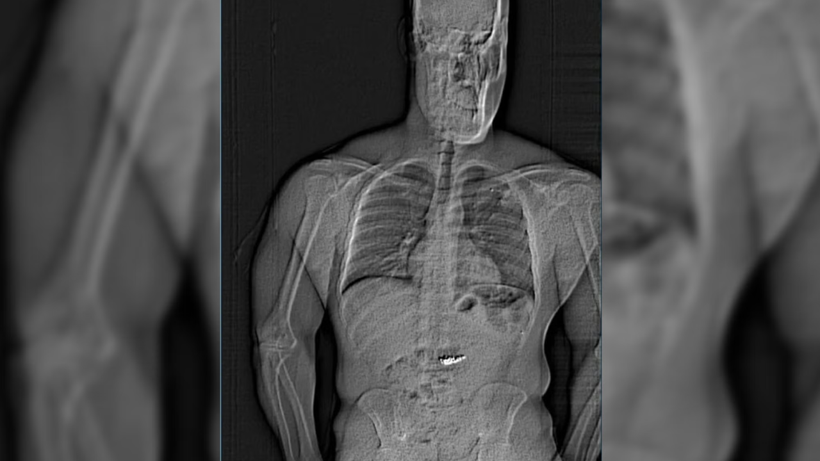

Şüpheli, cezaevine götürüldüğünde yapılan vücut taramasında midesinde "yabancı cisimler" olduğu tespit edildi. Polis, bunların çaldığı elmas küpeler olduğunu düşünüyor, ancak durumu doğrulamak için "doğal sürecin tamamlanmasını" beklemek zorunda.